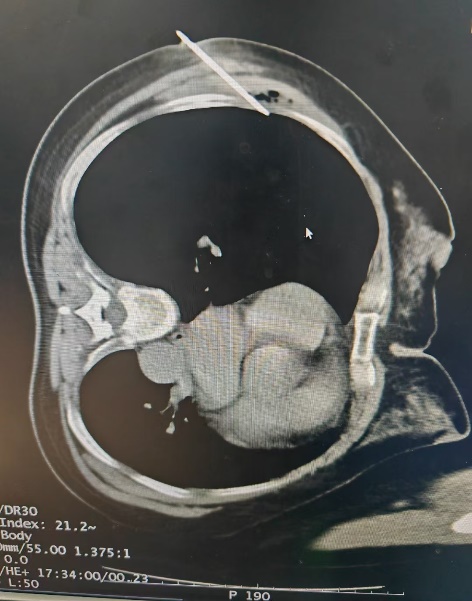

有一名女性患者,因咳嗽、咳痰40余天來院就診,行胸部CT提示:右肺上葉病灶,不排除肺癌可能。為進一步明確診斷,予以充分評估后,在CT引導下行經皮肺穿刺活檢術,病理結果顯示:(右肺)肺泡上皮異型增生,局灶結構紊亂,考慮腺癌,建議免疫組化六項檢查,為患者的后續精準治療提供了依據。